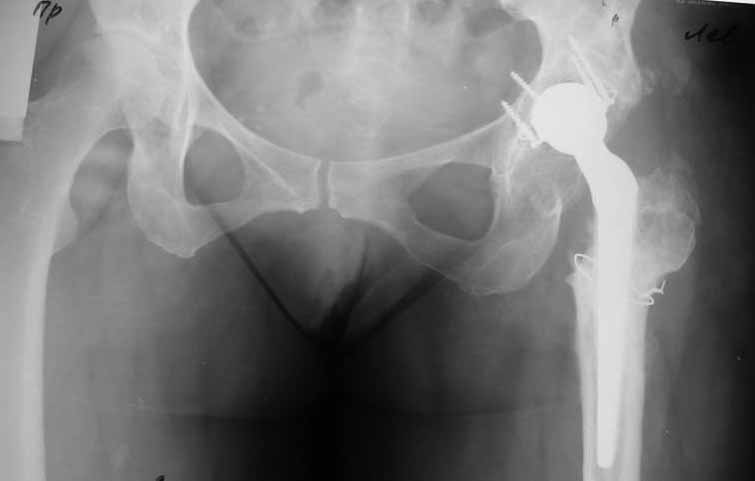

Пациентка 45 лет. Бесцементное эндопротезирование левого тазобедренного сустава 6 лет назад (впадина RM, Mathys, металл-металл, ножка Зульцеровская). За 10 лет до протезирования – коррегирующая остеотомия бедренной кости, которая не срослась в течение года до удаления пластины, а затем срослась в течение 3 месяцев иммобилизации в кокситной повязке. После протезирования получилось наблюдать пациентку почти постоянно, поскольку через 2 года синтезировал ей лодыжки на оперированной стороне, затем, через несколько месяцев удалил фиксаторы, а в 2009г. резецировал мениск на противоположной стороне. Боли все эти годы не беспокоили. Пациентка чуть выше среднего роста, вес тела нормальный. Физические нагрузки переносила хорошо. Работает на 7 этаже без лифта. Год назад экстирпация матки по поводу лейомиомы больших размеров. Несколько месяцев назад появились боли в области левого тазобедренного сустава. При рентгеновском и КТ исследованиях (июль с.г.) – нестабильность тазового компонента. От предложенной замены протеза пациентка на тот момент, слава богу, отказалась. Через какое то время боли в области левого тазобедренного сустава практически полностью прошли, а около 2 месяцев назад появилось ощущение патологической подвижности таза и боли в паху справа, которые через некоторое время уменьшились, а потом снова усилились после значительных физических нагрузок (много ходила по песку на пляже, носила тяжести). Ежедневно принимала диклофенак. На рентгенограммах – переломы правой лонной кости. Сейчас госпитализирована из-за болей в паху справа. Боли слева не беспокоят. На фоне снижения нагрузок в стационаре боли значимо уменьшились. Способна ходить без средств дополнительной опоры.

На представленных снимках тазобедренный сустав до и сразу после операции, затем 2 снимка 2009г., когда ничего не беспокоило, затем КТ 2-х месячной давности и вчерашние рентгенограммы обоих тазобедренных суставов.